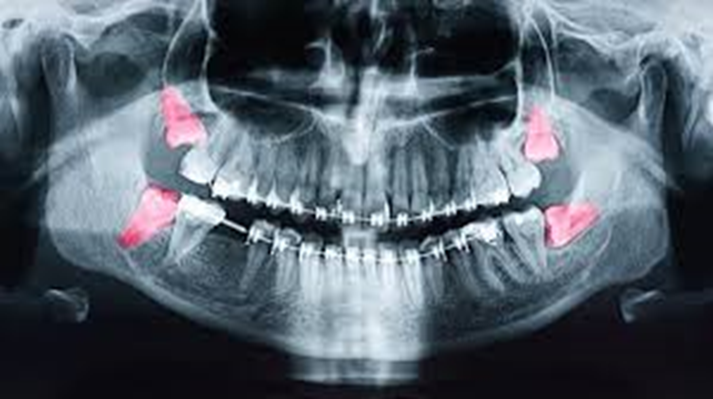

Impacted tooth: -

This is also one of the causes of toothache. It occurs

majorly due to the impaction of the third molar (wisdom tooth). The general age

of this pain is 18-25 years. Pain occurs due to

pressure by the tooth, when it doesn't get any path to come out in

occlusion or the proper space it needs in the arch.